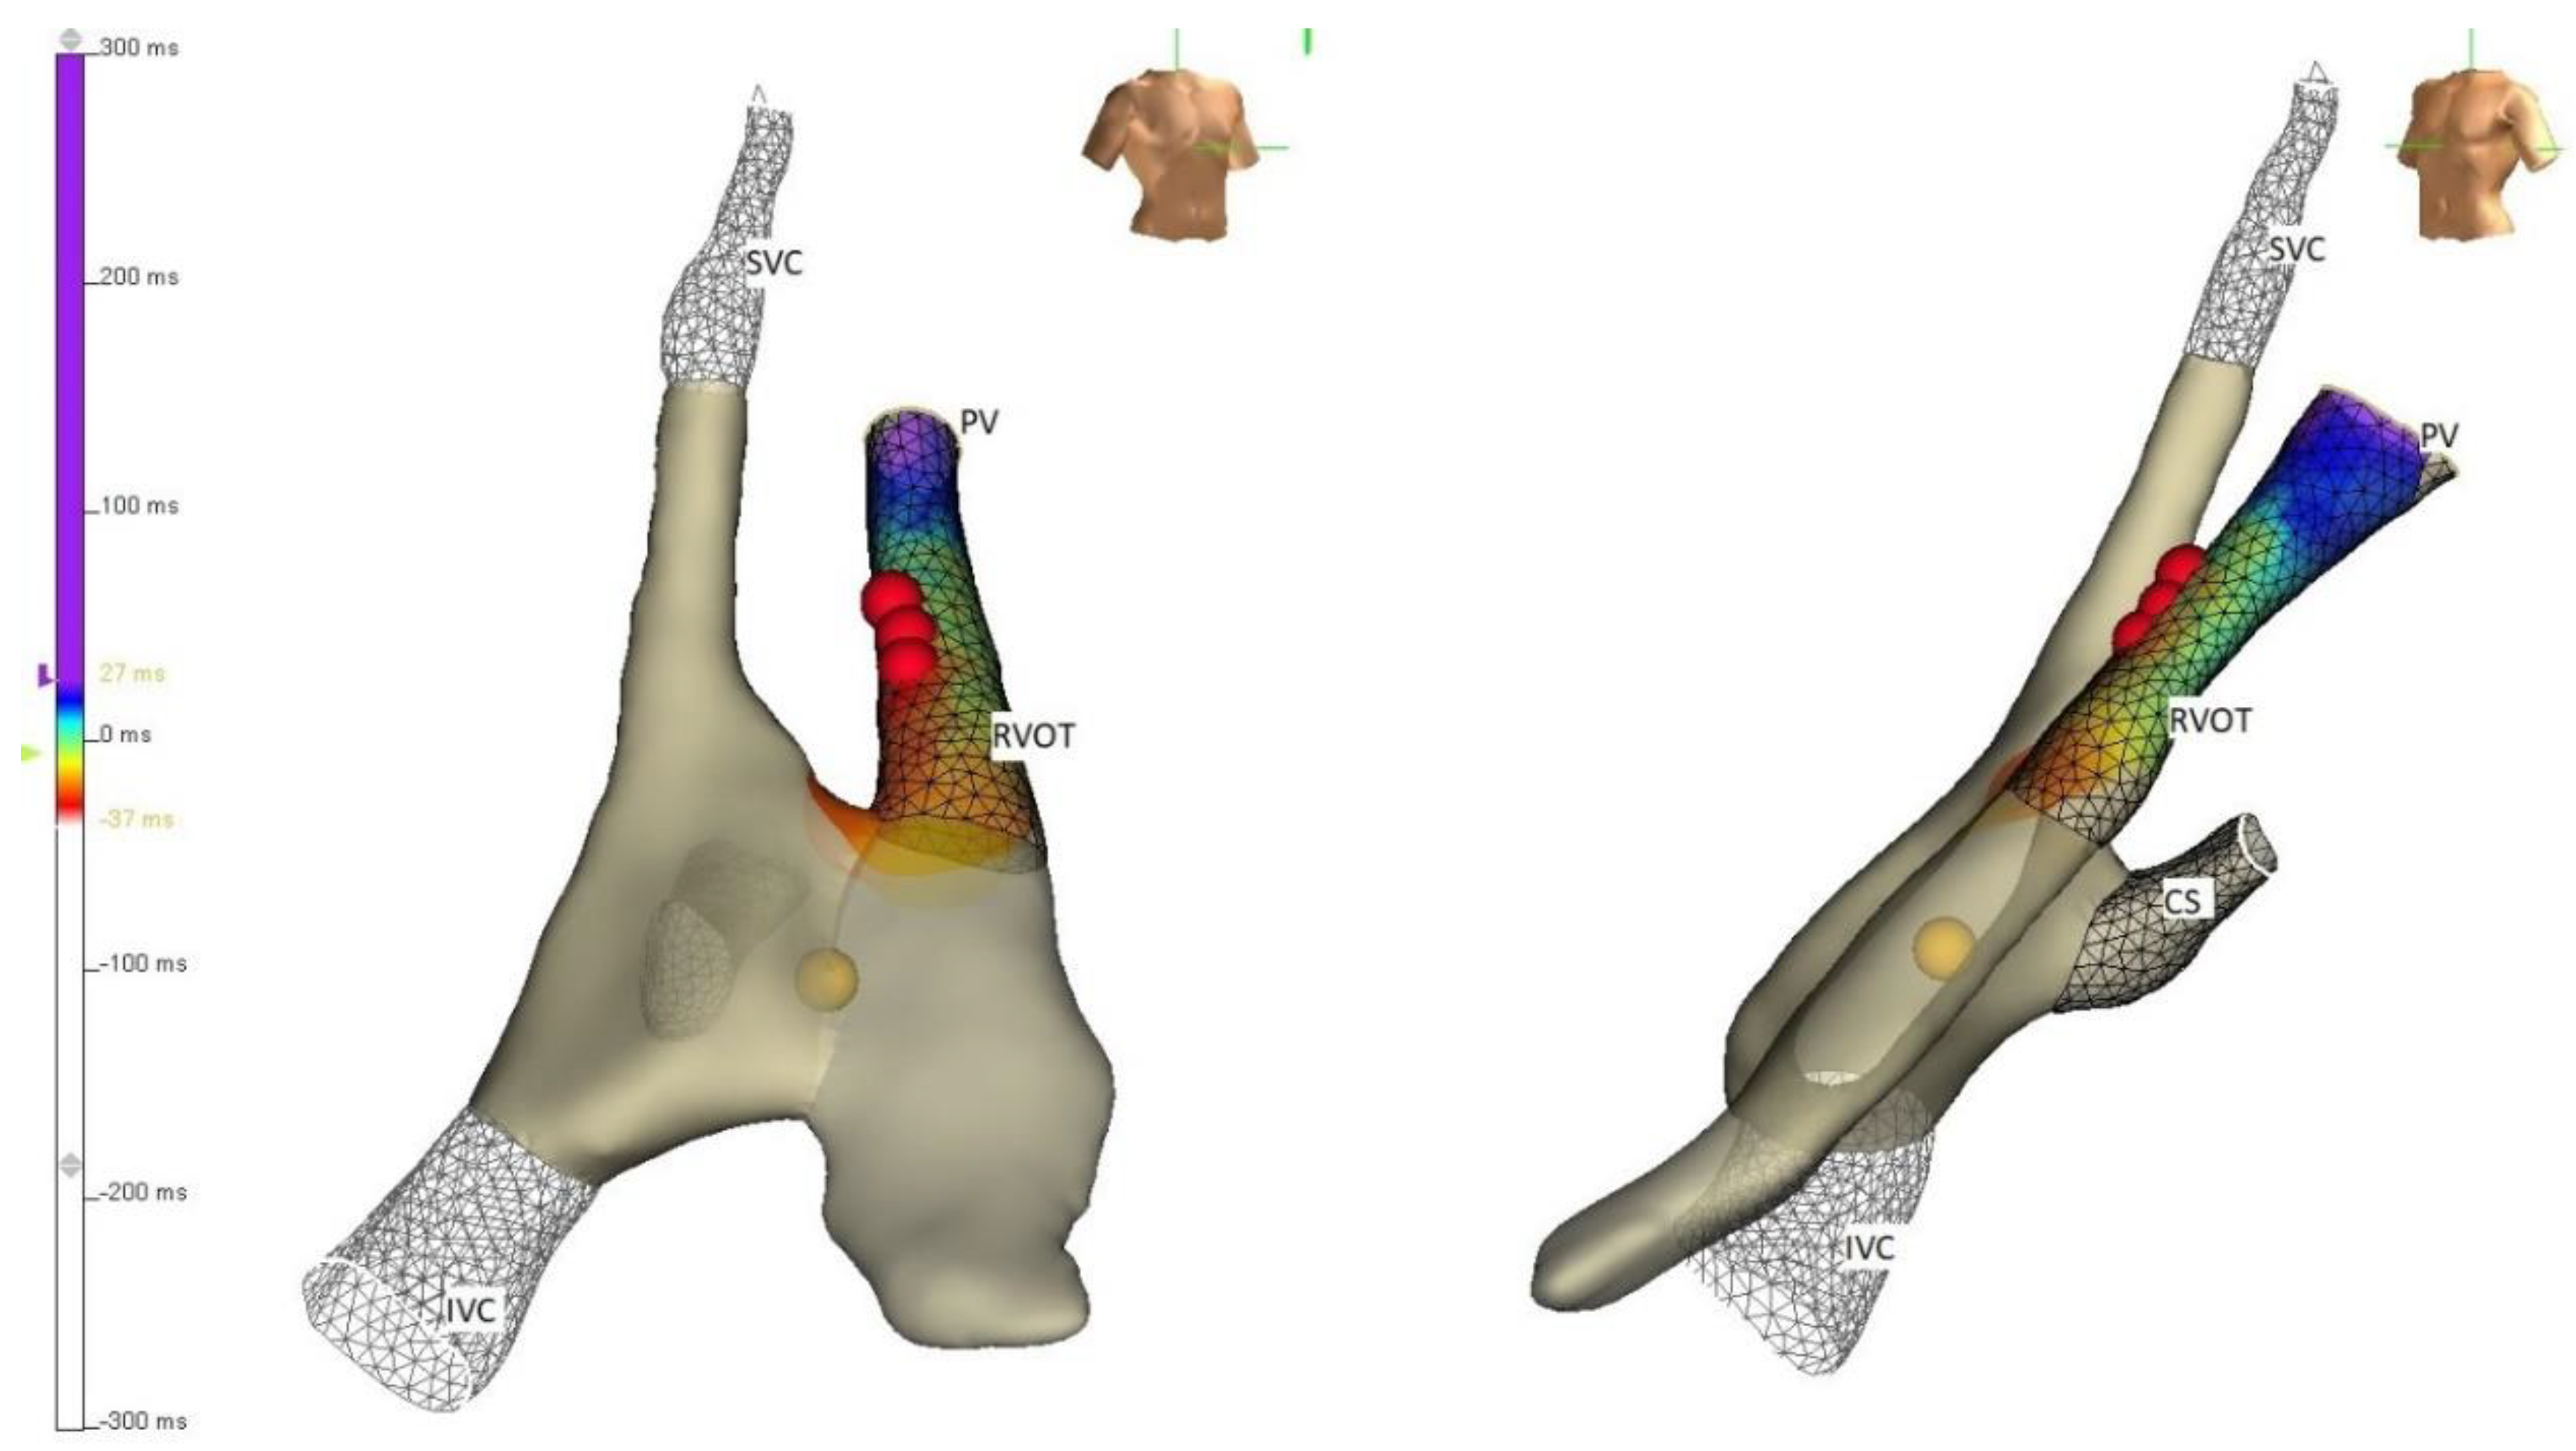

4. Strategies

5. Techniques

- Bansal, N.; Kobayashi, D.; Karpawich, P.P. Pulmonary damage following right ventricular outflow tachycardia ablation in a child: When electroanatomical mapping isn’t good enough. Pacing Clin. Electrophysiol. 2018, 41, 561–565. [Google Scholar] [CrossRef]